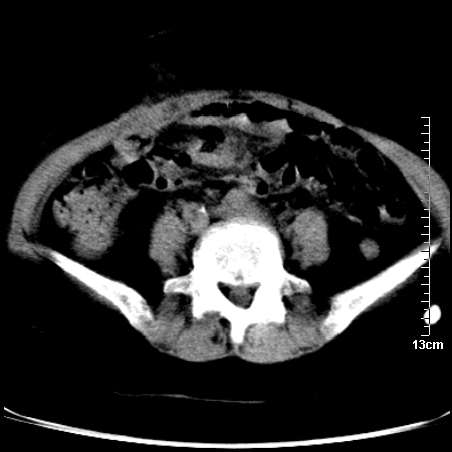

术前的疏忽,手术前诊断阑尾炎,但是没有常规做b超,导致术后1周检查发现 1。实性包块?2。腹腔术后脓肿?

病史:病人一周前诊断阑尾炎,未做b超,手术发现阑尾化脓,(没有留意有无包块),术后1周病人发热,血象:1.6万,做b超发现,随ct检查,上传图片

巨大囊实性包块,边界大部尚清楚,不太像脓肿的表现。应该做个增强检查除外盆腔肿瘤。

脓肿可能性大. 因回盲部区域化脓性兰尾切除残端感染改变征像与实性肿块关系密切.肿块上界至右下腹,下界至盆腔膀胱上缘, 如果是实性肿块在兰尾术中可能就会发现. 所以术后一周病人高烧, 白细胞增高,临床表现支持脓肿.

盆腔一边界大部份清晰囊实性肿块,其周腹脂未见确切异常,其一端与右侧附件相连。考虑右侧附件肿瘤。

如果能进行肠道准备就好了!盆腔内巨大囊实性包块,右前缘与周围肠管分界不清,病灶内前部的气体是否为肠管内气体形成的假象不能确定。

这么大一包快手术当中没有发现?值得怀疑!结合化脓性阑尾炎病史,首先考虑脓肿!不排外附件来源的肿瘤,建议增强扫描!!